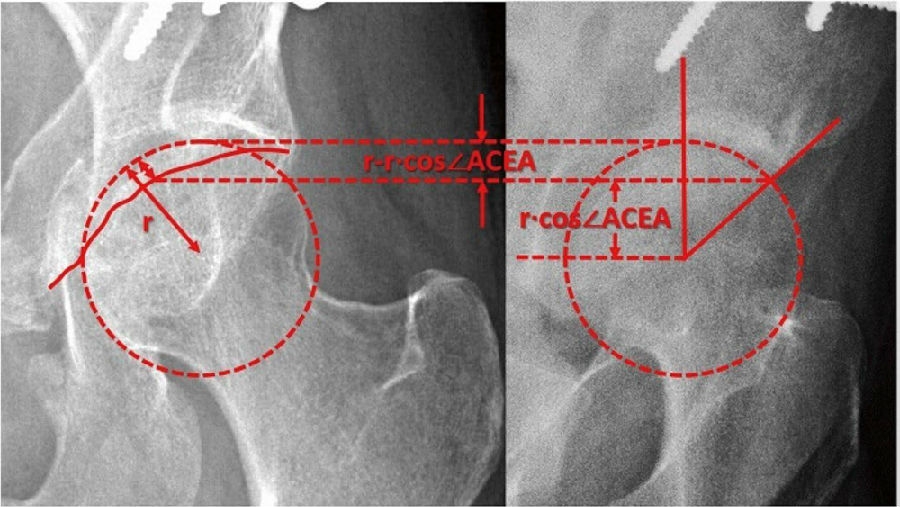

1.ACEA与CT三维前覆盖这两个指标不能相互替代[38],该研究由于没有考虑到平卧位时骨盆常会出现的前倾对结果的影响,待进一步改善。

2.ACEA与CT矢状面上前中心边缘角这两个指标不能相互替代[39]。

本部分中有一个观点需要大家关注,通过骨盆前后位片上前后壁的位置判断髋臼的前覆盖极其不准确。PAO术中,通常会通过交叉指数、交叉标志、前壁指数(AWI)和三分之一规则这4个盆骨AP X线片的指标判断前覆盖。该文章为了研究这些方法的准确性,回顾性分析了在2020年7月至10月期间接受髋臼周围截骨手术治疗髋关节发育不良的53名患者。分别在手术前和手术后6个月测量上述指标,并进行比较。纳入研究的53髋中,手术前交叉指数和ACEA(P=0.66)或交叉标志之间并无相关性。手术后,交叉指数和ACEA之间的相关性较弱(r=0.36,P=0.007),交叉标志和ACEA之间的相关性中等(r=0.41,P=0.003)。无论手术前后,AWI和ACEA之间的相关性都较弱(手术前r=0.288,P=0.036;手术后r=0.349,P=0.011)。而且,使用三分之一规则来评估前覆盖时,其与ACEA的一致性也不高。

该研究告诉我们,因为在骨盆前后位片上观察髋臼前壁会受到髂前下棘影的影响。通过AP X线片判断的髋前覆盖与通过FP(假斜位)X线片判断的ACEA很不一致,尤其是在手术前。因此建议在判断髋前覆盖时,应常规采用FP X线片。